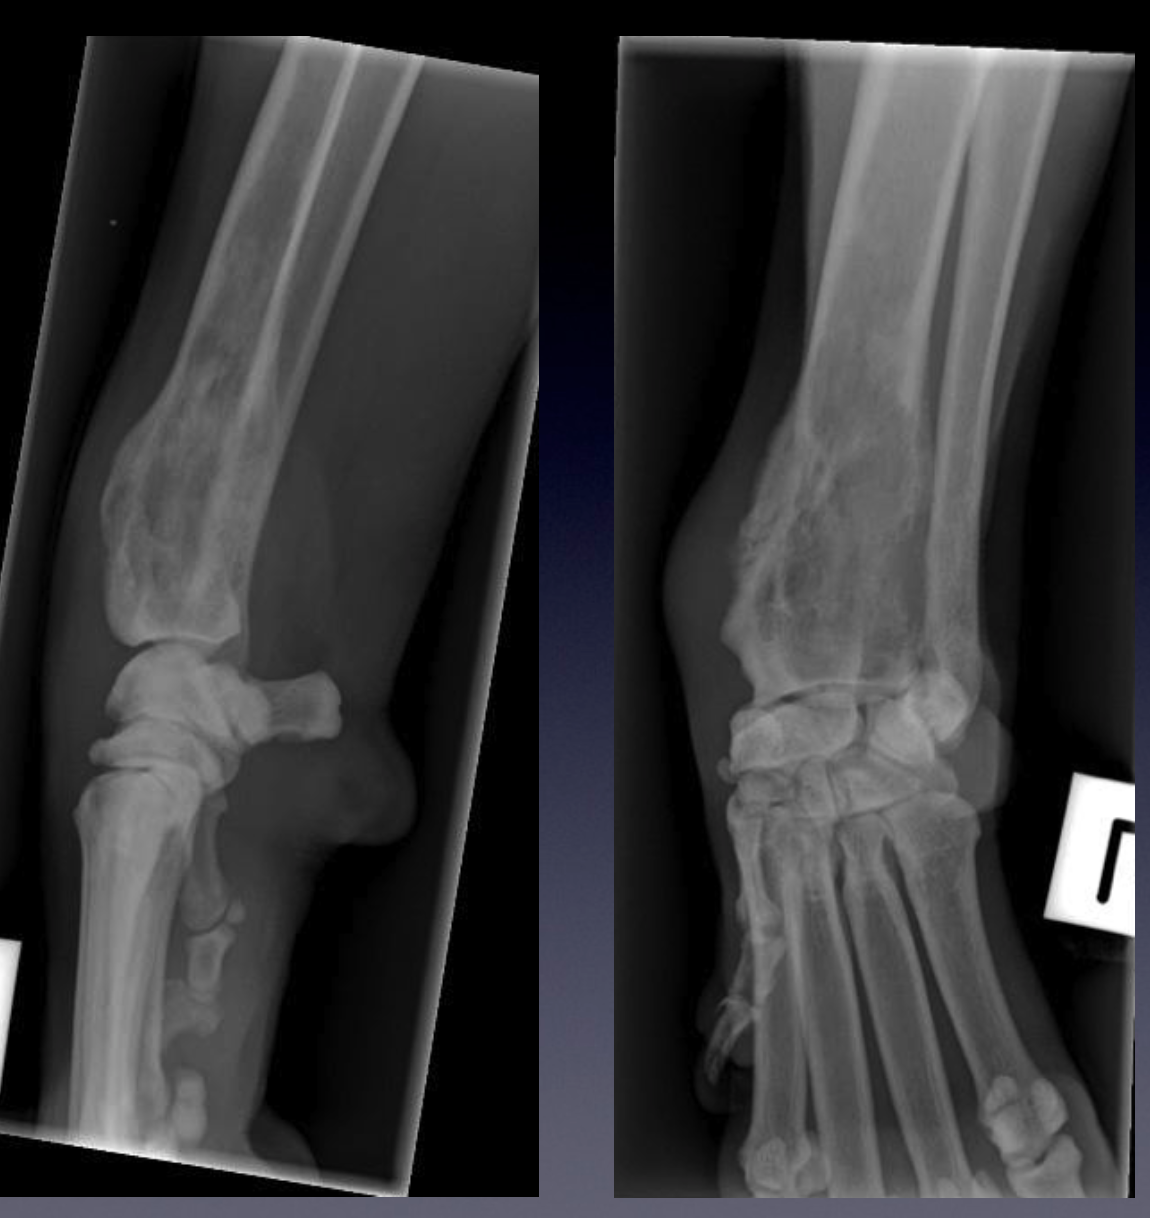

Case 2: Patient 227876

VIEW?

Compare these radiographs to the normal example of a carpus.

Please identify the following:

•

Soft tissue swelling centred on the distal aspect of the radius

The reduced opacity and loss of trabecular structure of the distal radial metaphysis

The large area of irregularly margined lucency in the distal metaphysis, consistent

with moth-eaten lysis

the long transition zone proximally with multiple small radiolucencies extending

toward the diaphysis, consistent with permeative lysis

Lysis of the distal radial cortex

Note that although the bone lysis extends into the distal radial epiphysis, it does not

breech the thin sub-chondral bone plate and does not cross the joint

Periosteal new bone (PNB) formation along the cranial and medial aspect of the

distal radial metaphysis. This PNB is continuous and solid on the cranial aspect,

and palisading on the medial aspect.

How many bones are affected?

Although the periosteal reaction identified in this lesion is continuous, the patterns of

bone lysis are aggressive. A lesion should be classified by it’s more aggressive

characteristics, thus this is an aggressive bone lesion.

What are you two main groups of differential diagnosis?

Which one is more likely and why?

How would you proceed with management of this case?

Mediolateral and dorsopalmar projections of the carpus of a skeletally mature dog.